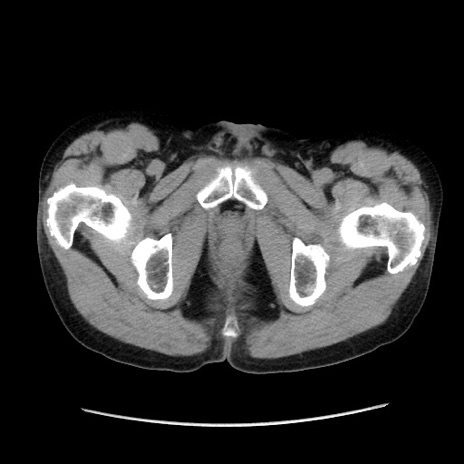

冠状断像

【症例】40歳代 男性

【主訴】腹痛

【現病歴】4時間ほど前に電車に乗車中に臍部上より腹痛出現。徐々に増悪し起立困難となり、救急外来受診。生ものは数日食べていない。今朝お雑煮を食べた。

【身体所見】BT 36.8℃、BP 117/84mmHg、HR 91/min、SpO2 97%、苦悶様、腹部:臍上部広範囲圧痛あり、反跳痛±

【データ】WBC 8100、CRP 0.03